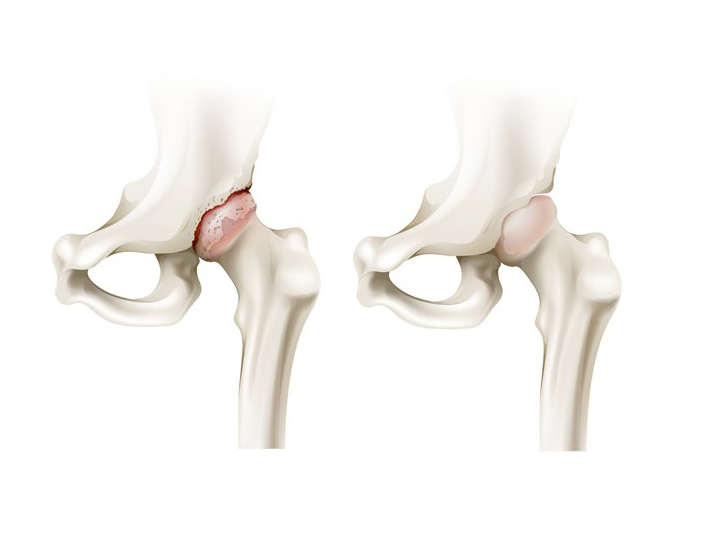

Grafika przedstawiająca chory i zdrowy staw biodrowy

Torebka stawowa wypełniona jest płynem, zwanym mazią, produkowanym przez błonę maziową, w którym zawieszone są komórki tłuszczu i mucyna – składnik, znajdujący się również np. w ślinie, który nadaje lepkość i ma zdolność tworzenia żeli. Ta lepka i płynna zawartość wypełnia przestrzenie między kośćmi, dzięki czemu są blisko siebie, ale tarcie jednej o drugą jest zniwelowane. Wszystko jest dobrze – i nie czujesz, że w ogóle masz te stawy! – jeśli chrząstki w panewce i na głowie kości ślizgają się jedna o drugą, mazi jest wystarczająco dużo, a grubość wspomnianych chrząstek jest odpowiednia. Problem zaczyna się, gdy chrząstka po latach wiernej służby zaczyna się zużywać, a na kościach pojawiają się, bardzo powoli, bo proces ten trwa latami – kostne wyrostki, zwane osteofitami. U różnych osób dochodzi do tego w różnych momentach. Jeśli w czasie, gdy byłeś niemowlakiem stwierdzono u Ciebie dysplazję panewki biodrowej (m.in. dlatego dzieci wkrótce po urodzeniu są badane pod tym kątem przez ortopedów), przeszedłeś ciężkie złamanie w obrębie biodra i głowy kości udowej albo chorujesz na takie choroby, jak reumatoidalne zapalenie stawów czy hemofilię – może to być tzw. wtórna choroba zwyrodnieniowa stawu biodrowego. Jednak większość przypadków tego schorzenia to odmiana pierwotna, która związana jest z wiekiem i starzeniem się organizmu. Chrząstki w całym ciele zużywają się, przez co tracą swoje funkcje amortyzujące, mazistego płynu jest mniej albo zmienia swoją konsystencję i dochodzi do wrażenia, że kość trze o kość. Efektem jest ból, który potęguje to, że na biodrach, jak na solidnym, ale elastycznym stropie, utrzymuje się ciężar ciała.